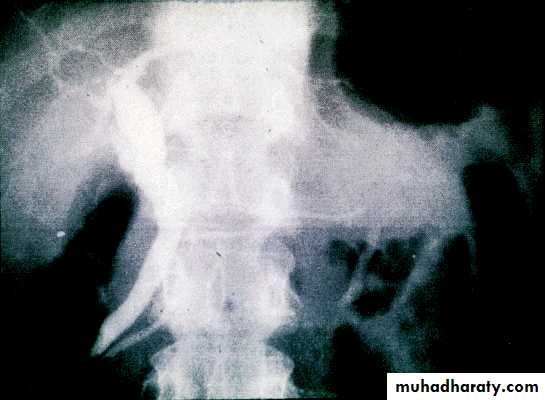

• Barium swallow & meal

Normal liver Isotope scan